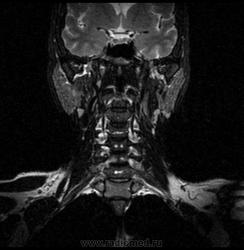

06.06.2011 МРТ - головы и шеи.

Пацентка 36 лет, с жалобами на припухлось в околоушной области справа.

Проблема в том, что перед челюстно-лицевым хирургом стоит распространенность любого объемного процесса, в данном случае все упирается в возмможную травму лицевого нерва и конечно же с дальнейшим его парезом, а ведь женщина  еще молодая. Образование имеет тонкостенную оболочку, по структуре неоднородно, с наличием кальцината, при этом МР-сигнал от окружающих анатомических структур(как костных так и мышечных) не изменен, т.е. об инфильтративном росте речи не идет, в какой то степени доброкачественное. В конкретном случае лицевой нерв с ретромандибулярной веной просто несколько оттеснен.

По гистологии аденома околоушной слюнной железы, но после удаления пока сохраняется парез лицевой мускулатуры, возможно временный.